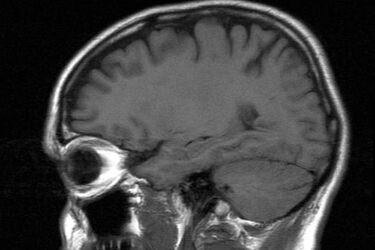

Fot: freeimages.com

Szpital psychiatryczny w Choroszczy przebuduje i doposaży oddział rehabilitacji neurologicznej.